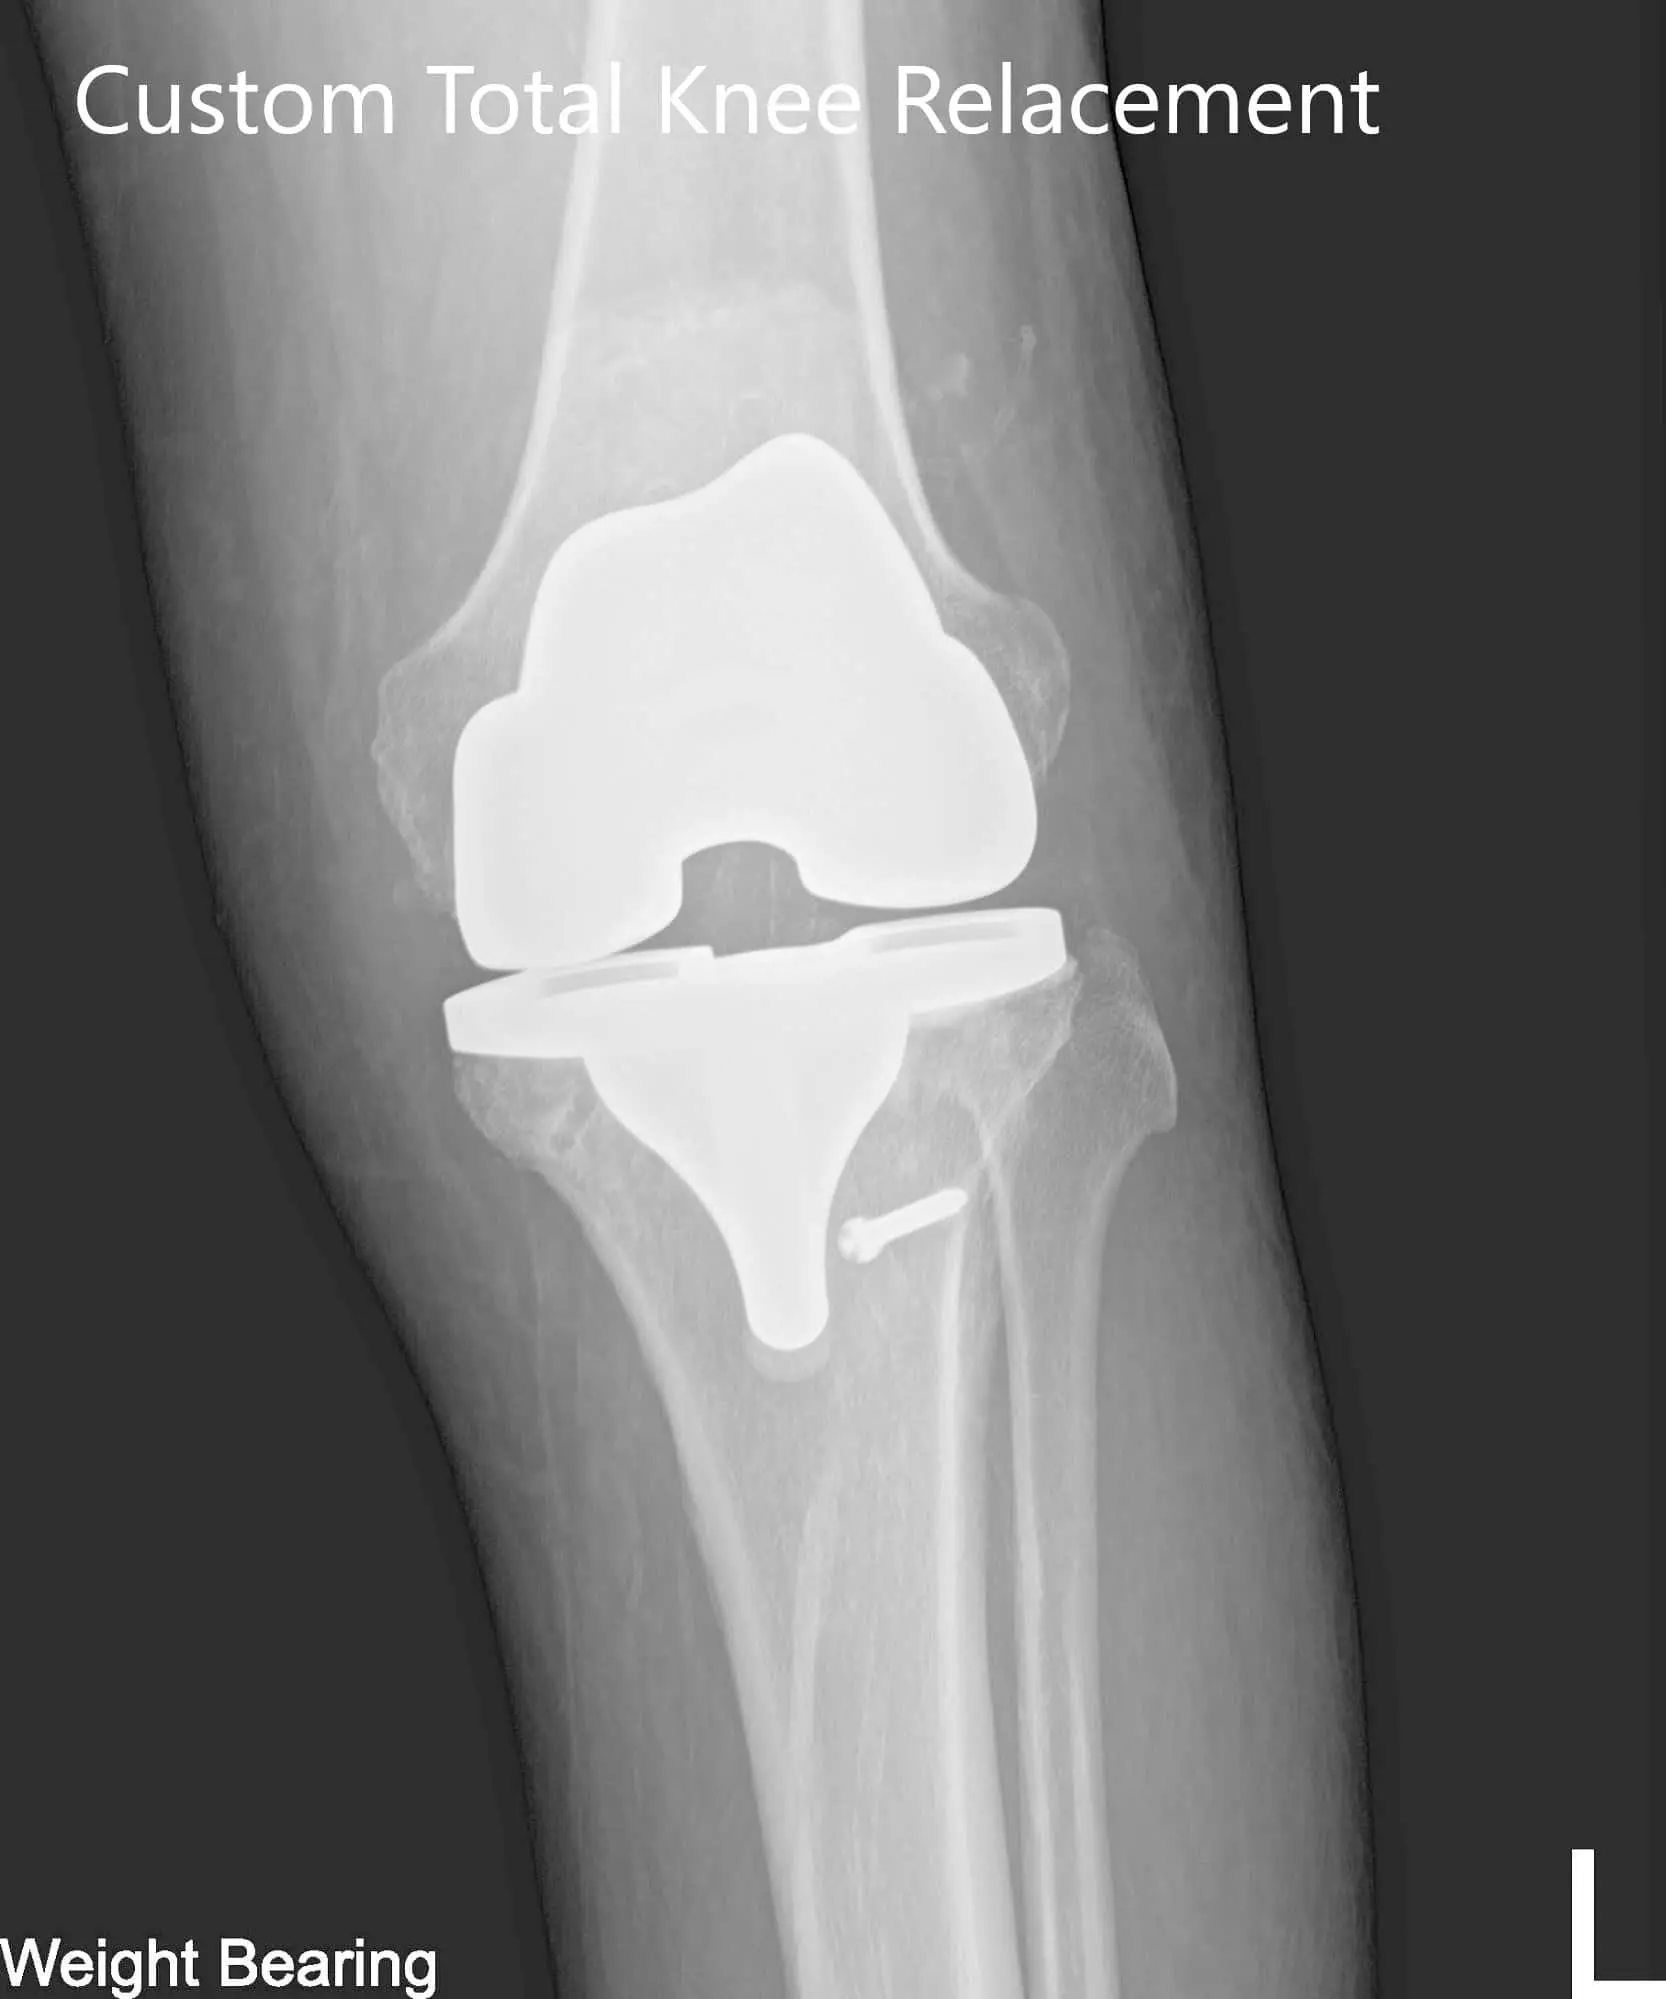

Implant – Left total knee arthroplasty using custom femur, custom tibia, patella, and 6-mm polyethylene

Postoperative X-ray of the left knee showing AP and lateral viewsPostoperative X-ray of the left knee showing AP and lateral views - img 2

Postoperative X-ray of the left knee showing AP and lateral views

The patient had an expedited post-operative recovery. She was bearing weight walking with support the same day. Her pain was well managed on medications and she was started on aspirin 325mg BID for deep vein thrombosis prophylaxis. On her subsequent visits, she had her staples removed. Her surgical wound was clean, dry and intact.

She was started on physical therapy and home exercise program regime. The patient was compliant with the regime and demonstrated a full range of motion. She was happily back to work and enjoyed her visits to the supermarket walking. She was able to continue her daily activities and was enthusiastic about the results. She was advised to follow up for the replacement of the right knee.